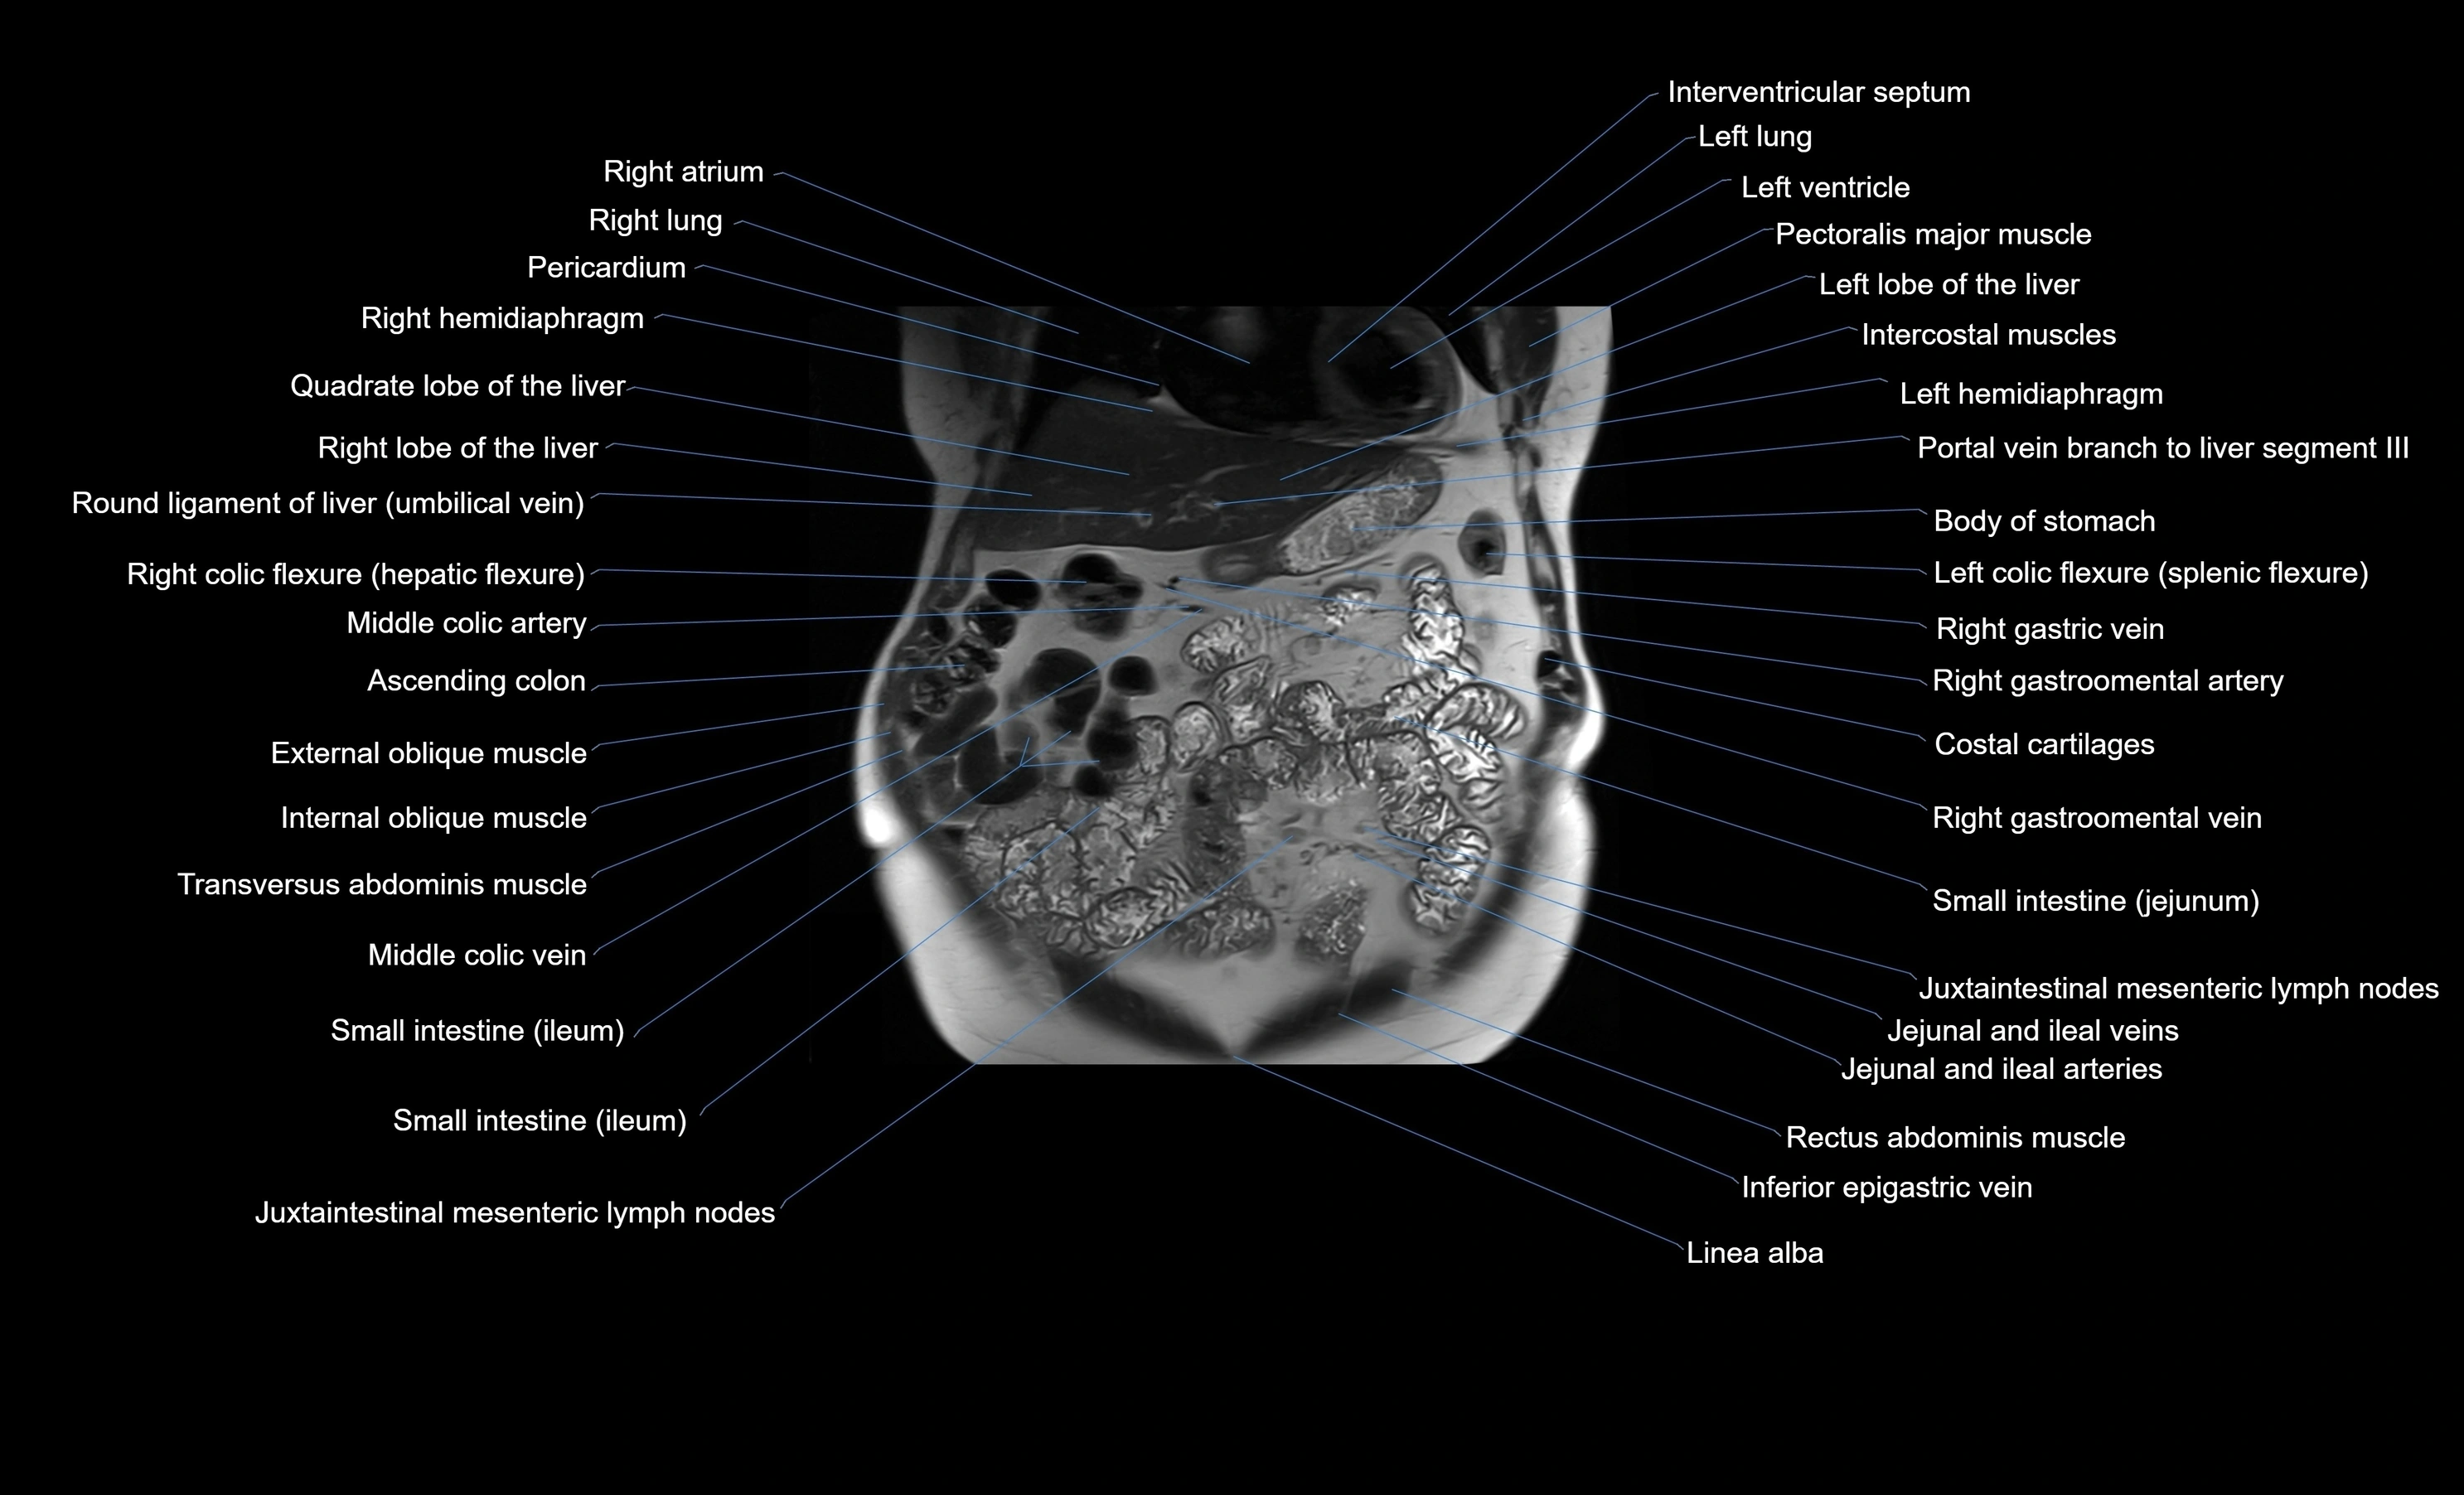

- Ascending colon

- Ileum

- Jejunum

- Left colic flexure (splenic flexure)

- Linea alba

- Middle Colic Vein

- Middle colic artery

- Rectus abdominis muscle

- Right colic flexure (hepatic flexure)

- Spleen

- Transverse colon